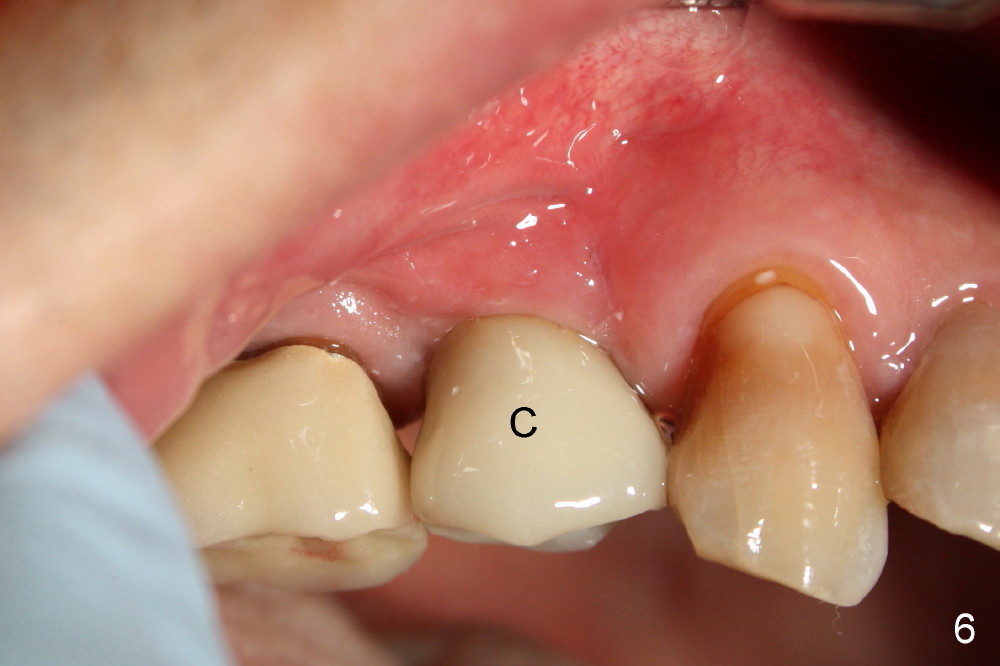

A single crown is cemented 3 months postop (Fig.6 C). Fig.7 is taken 6 months post cementation.